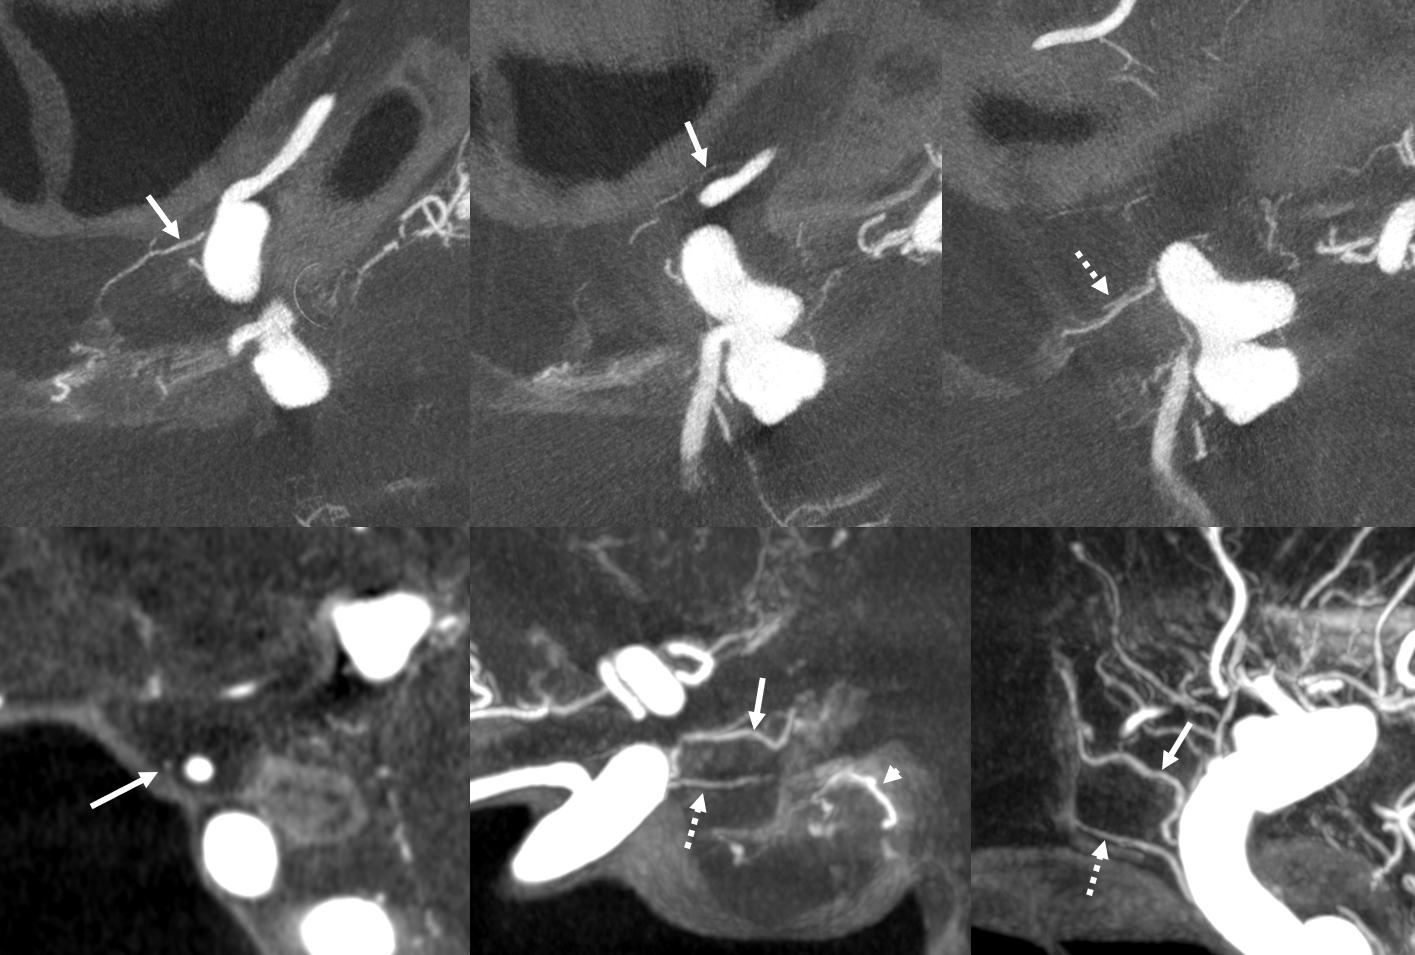

What supplies the bulk of optic nerve? Central Retinal artery is for the distal portion of nerve and retina. What about the rest — intracranial, intracanalicular, proximal intraconal segments? The answer is not clear (let me know if you do), but i believe the bulk of it comes from the superior hypophyseals. It is probably in balance with the recurrent branch of the central retinal artery. Below is an example of an especially prominent proximal-most superior hypophyseal (arrows) supplying the pituitary stalks and optic nerve in the canalicular and intracranial locations. Note how well one can see the branch in coronal view (bottom left image). In this case there are two large superior hypophyseals — the more distal one (dashed arrows) supplies predominantly the pituitary stalk. The inferior hypophyseal artery is marked by arrowhead. Lower right image is coronal.

Movie is the best way

Here too superior hypophyseal (arrow) supply of the intracranial optic nerve (oval) and possibly chiasm is shown definitively (lower right image is coronal)

No annotations

Best seen in this movie (pause to scroll)

Pattern of optic apparatus supply and unusual hypophyseal ILT vessel

VR — the anterior-most branch of the superior hypophyseals is usually the largest (arrow). The others are too small to see on a VR image

MIPS. The anterior, proximal-most branch (arrow) tends to supply the optic nerve (white oval), while the more posterior branches (dashed arrows), when present, supply more posterior structures such as chiasm and tract (dashed oval)

A highly unusual branch originating from ILT region swings underneath the cavernous ICA and supplies the floor of the pituitary fossa. Yet unknown, as far as i know

More Optic Nerve Supply — its easier to see on MIPS, but with the right windowing, and stereo, VR imaging is also possible. Here, there are 3 superior hypophyseals seen. The anterior-most (arrow) is usually the largest, suppling the optic nerve (dashed arrow) and chiasm (ball arrow). The middle and posterior hypophyseals (arrowheads) supply the stalk.

Stereo of VR image. Same arrows. The stalk is open arrow.

Another patient — also 3 arteries. Cave origin of the anterior-most (arrows) one. The middle one (arrowheads) also supplies the optic nerve. The posterior one (dashed arrows) is for the stalk.

VR images (stereo pair on bottom). The cave origin of the anterior branch is most beautifully seen in the upper right image.